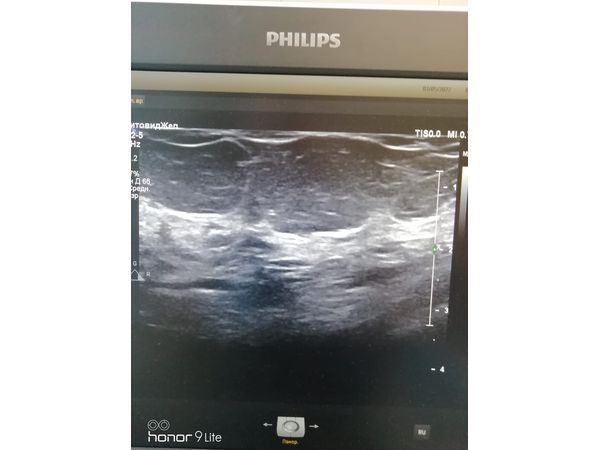

УЗИ молочных желёз от 4 марта показало:

- доброкачественные изменения в правой и левой молочных железах;

- признаки мастопатии по кистозному типу;

- большая единичная киста в верхней части правой молочной железы — размером 19×8,5×18 мм;

- кровоток не определялся.